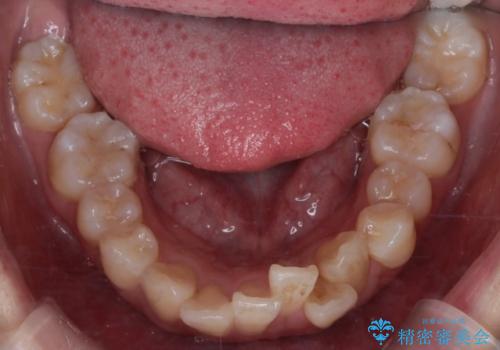

- 八重歯(叢生)と、上下の歯の中心線(正中)がずれていることを主訴にご来院されました。精密な検査の結果、歯列全体のスペースが大幅に不足しており、八重歯を正しい位置に配列し、正中のズレを改善するためには、上下左右の第一小臼歯を抜歯する必要があると診断。装置には、目立ちにくい審美ワイヤーを使用し、見た目を気にせず、機能性と審美性が完璧に整った咬み合わせを目指す治療計画を立案しました。

今回の矯正治療では、まず計画通り上下左右の小臼歯4本を抜歯し、八重歯や正中のズレを解消するための十分なスペースを確保しました。装置には、目立ちにくい白いブラケットとワイヤーを使用した審美ワイヤー矯正を採用。

八重歯: 突出していた八重歯を歯列内に誘導し、デコボコを解消しました。

治療の結果、長年気にされていた八重歯と正中のズレが解消し、機能的にも整った理想的な歯並びを獲得。目立たない装置で治療を完遂し、自信を持って笑える美しい笑顔を手に入れていただけました。